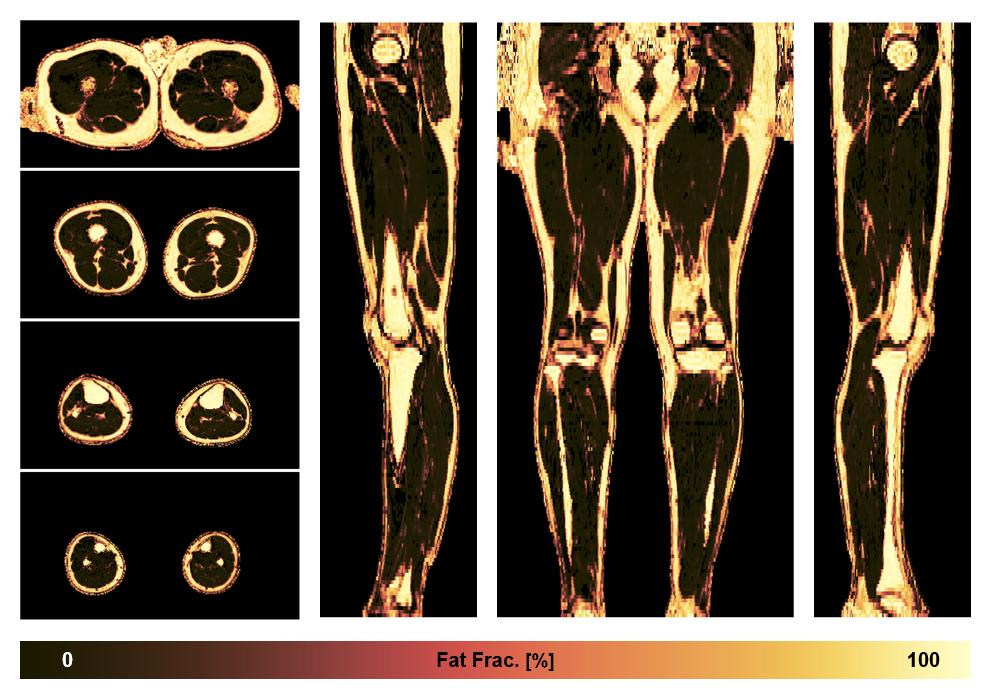

• Fat fraction

The fat fraction of the lower extremity obtained from the dixon reconstruction for muscle water fat quantification.